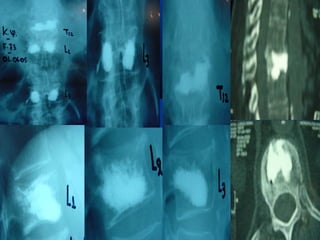

One level

Discoplasty

Level L3 - L4 Level L4 – L5 Level L5 – S1

Level L3 -L4 Level L4 – L5 Level L5 – S1